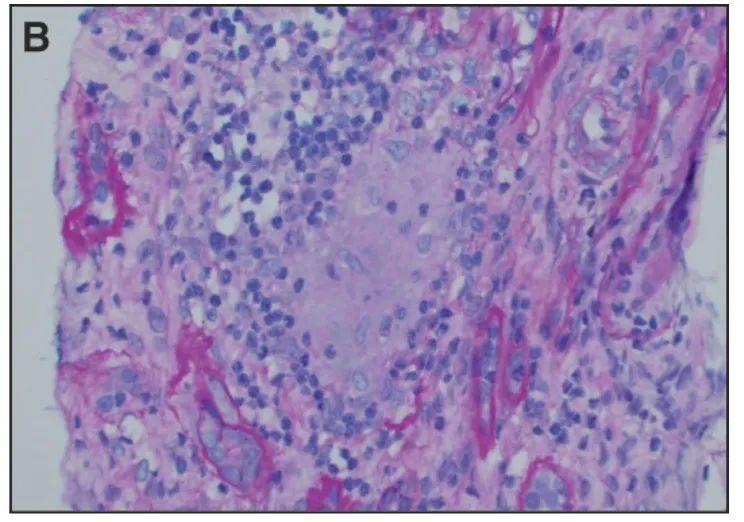

Caso típico de GNRP em paciente idosos. Vendo a imagem, qual seria sua primeira hipótese diagnóstica?

Valkercyo Feitosa